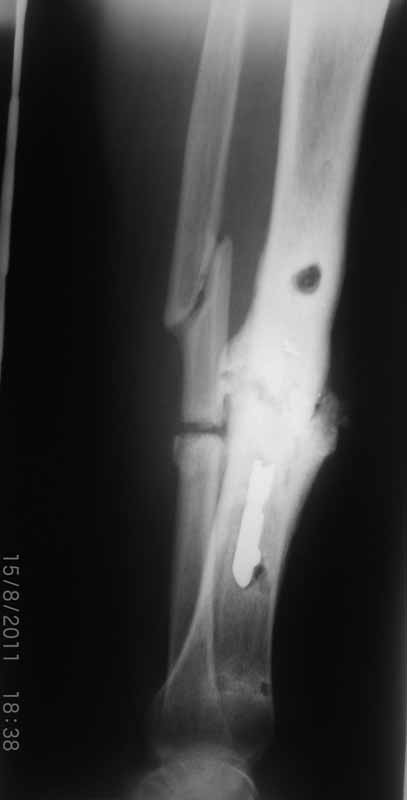

Иван 17 Август 2011, 20:17

Уважаемые коллеги благодарю Вас за проявленный интерес к данной проблеме! Пересылаю Вам внешний вид правой голени.

Как-то вот нет уже желания открываться в зоне ложного сустава. Мы бы

попытались сделать закрыто. Винт в дистальном отломке удалить через прокол.

Кусок гвоздя оставить. Новый гвоздь (солидный), возможно с покрытием.

Коллеги!

Место ложного сустава не выглядит гипертрофическим. Нет разрастания костной мозоли.

Закрыто все сделать не удасться. Фрагмент стержня нужно удалить, придется трепанировать кортикал и удалять фрагмент конец стежня. Свободная костная пластика - высой риск нагноения. Как вы думаете, может микрохирургически заместить дефект трансплантом из малоберцовой кости на сосудистой ножке это выход? В приложении статья о замещении костных дефектов трансплантатми на сосудистой ножке. описывают васкуляризованную костную пластику при ложных суставах.